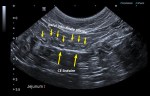

latérale_annotations